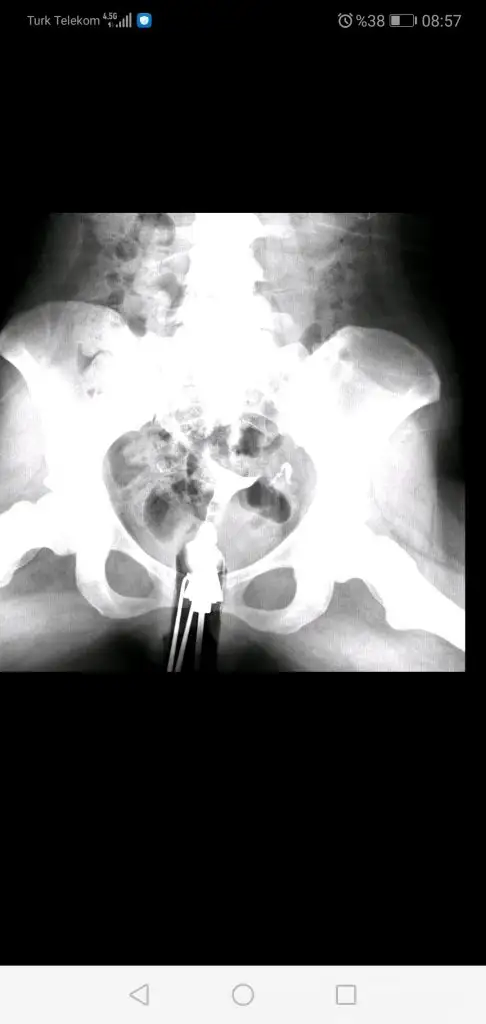

Canım bak 2 ve 3 ilk vuruşlardaki hali en baştaki de 4. Vuruştan sonra çekilen görüntü. Geçiş görünüyor ama açıldı mı bilmiyorum. Doktor lap a gerek yok şuan dedi. 4 ay sonra bi daha hsg çekilcem kendi isteğimleCanım senin tüptekş yapılıklık rahim gilmi ile açıldı mı peki?

Geçiş varsa açılmıştır kuzumCanım bak 2 ve 3 ilk vuruşlardaki hali en baştaki de 4. Vuruştan sonra çekilen görüntü. Geçiş görünüyor ama açıldı mı bilmiyorum. Doktor lap a gerek yok şuan dedi. 4 ay sonra bi daha hsg çekilcem kendi isteğimle

Umarım canım valla çoğu doktor sıkıntı yok yapışıklık varmış açılmış diyor instada bi kadına attım o da tam peritonel geçiş yok gibi falan dedi ama ben yine aşılamadan önce çekilcem hsg bi son hali ne durumda göreyimGeçiş varsa açılmıştır kuzum![]()

Açılmış canım geçmiş sıvı karın boşluğuna iki taraftan daCanım bak 2 ve 3 ilk vuruşlardaki hali en baştaki de 4. Vuruştan sonra çekilen görüntü. Geçiş görünüyor ama açıldı mı bilmiyorum. Doktor lap a gerek yok şuan dedi. 4 ay sonra bi daha hsg çekilcem kendi isteğimle

Umarım canım ben de öyle düşünmek istiyorumAçılmış canım geçmiş sıvı karın boşluğuna iki taraftan da